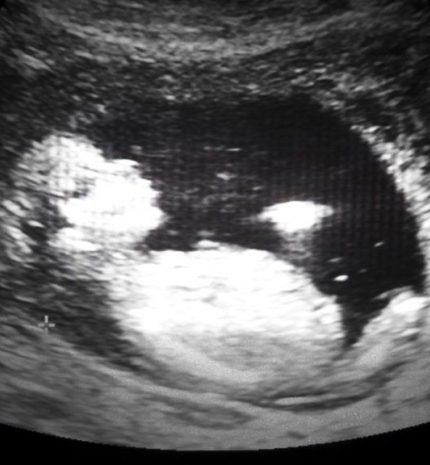

Videóra vették, ahogy az anyaméhben az ikrek egymást püfölik

Vajon jóban lesznek, ha megszületnek?